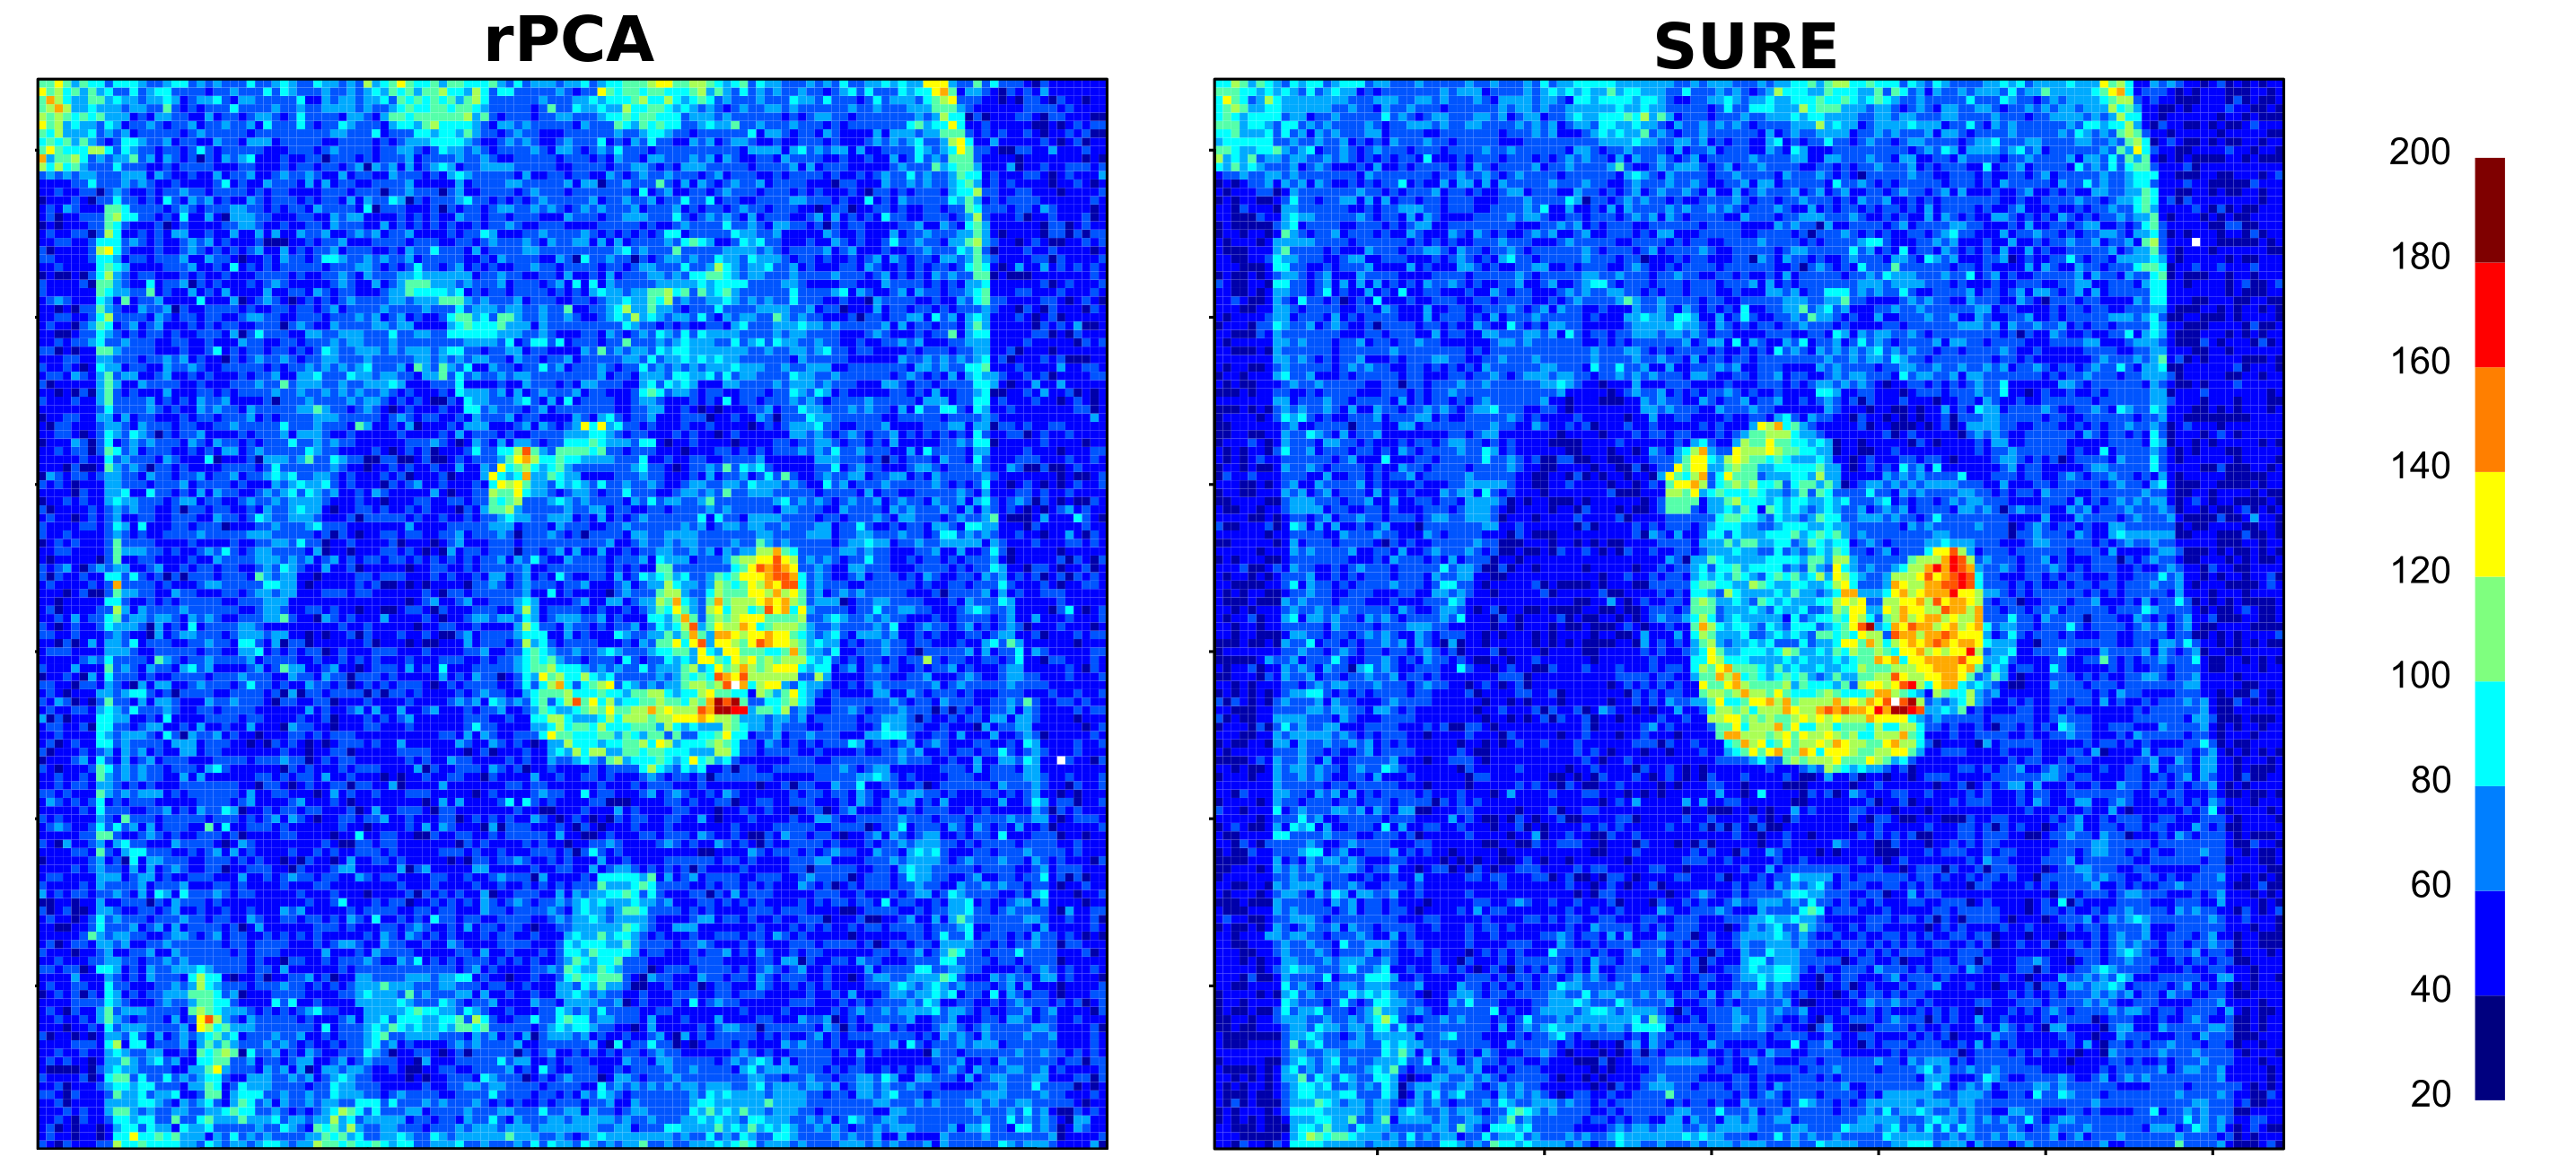

In addition, we can consider the worst-case absolute error through time (Figure 7), which is the highest residual error for each pixel at any time. The SURE method has a particularly high residual error in the area near the myocardium which is an area of high motion. The residual error is globally lower for rPCA than for SURE, and it is overall lower in the myocardium area.

Refer to caption

Figure 7: Worst-case absolute error through time of the image estimations by rPCA and SURE.